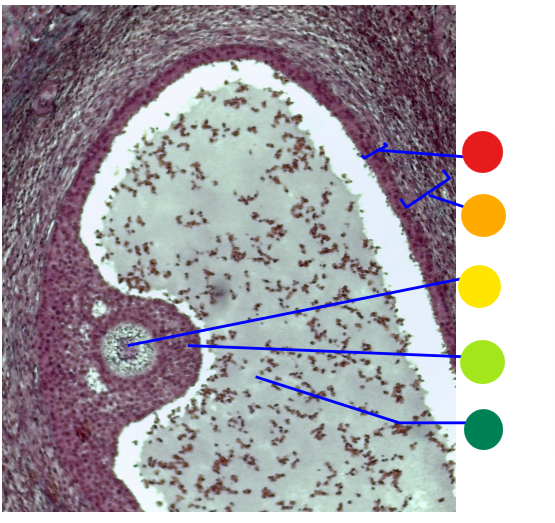

what is this

secondary follicle

what is this

tertiary follicle

red

tunica albuginea

orange

primordial follicles

red

primary follicle

orange

secondary follicles

what is this

tertiary follicle

What is this

mature follicle